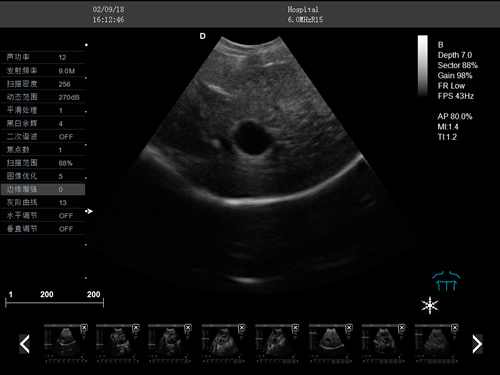

動物寵物超聲診斷儀

·牛羊馬豬犬貓及多種家禽、實驗動物、野生動物、及部分水生動物

·中小動物的肝、膽,脾、腎、膀胱、子宮、妊娠等各組織器官的檢查和病變的診斷